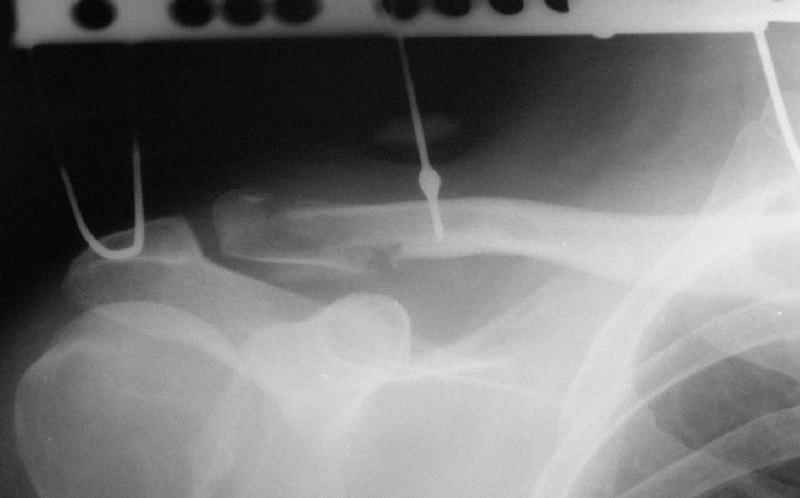

Re: Несросшийся перелом ключицы

Alexander Chelnokov 10 Ноябрь 2005, 01:06

При данных повреждениях возможно применение как АВФ, так и открытые способы лечения. Выбор в основном определяется давностью травмы, требованиями больного и отношением хирурга к тому-или иному способу лечения. В данном случае, учитывая смещение фрагмента с прикреплением кл-кл связки каудально, необходимо было "утопить" проксимальный отломок, что и сделано АВФ.